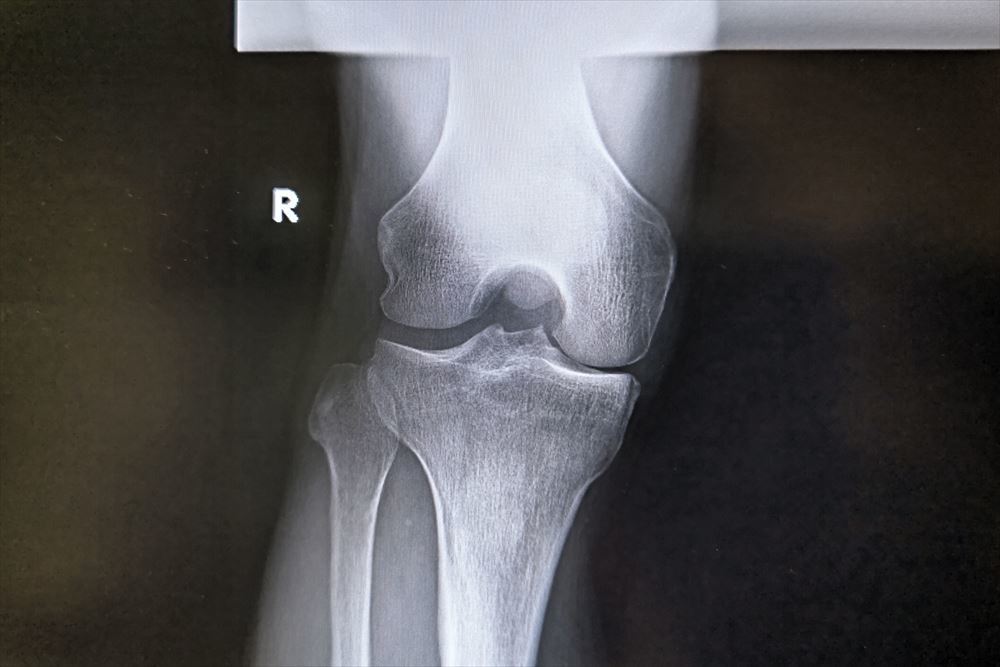

私も右変形性膝関節症です(前にも上げたかな)

町医者に骨切り術のセンセを勧められましたがもう少し年を取ってから人工関節か骨切りを決めましょうと現在はヒアルロン酸注射を月一に打って薬も飲んでます。

骨切りはO脚が酷いので脛の骨は2本とも切らないといけないとか。

【右膝.jpg : 55.0KB】